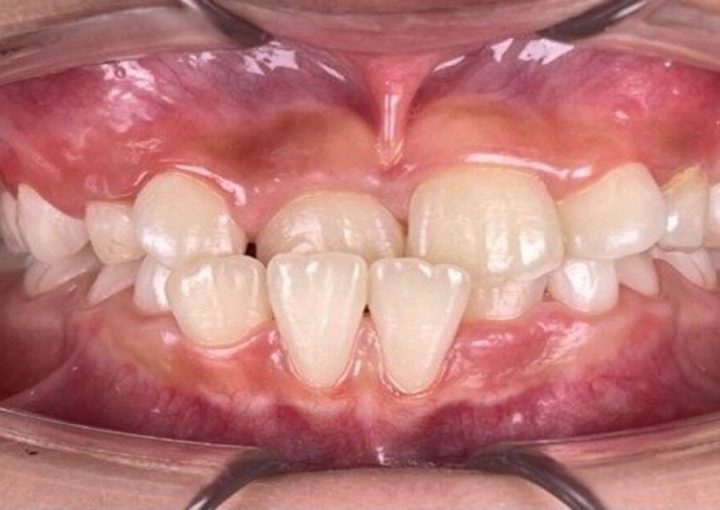

Ready to fix Dental Spacing?